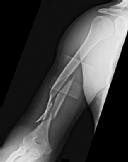

Figures 1 and 2 are the radiographs of a 19-year-old man with a closed right humeral shaft fracture as well as a right femoral shaft fracture and a left ankle fracture-dislocation after a motor vehicle collision. On initial examination, he is noted to have a complete radial nerve palsy of his right upper extremity.

Postoperative radiographs are shown in Figures 3 and

The working length of the plate is best described as the length